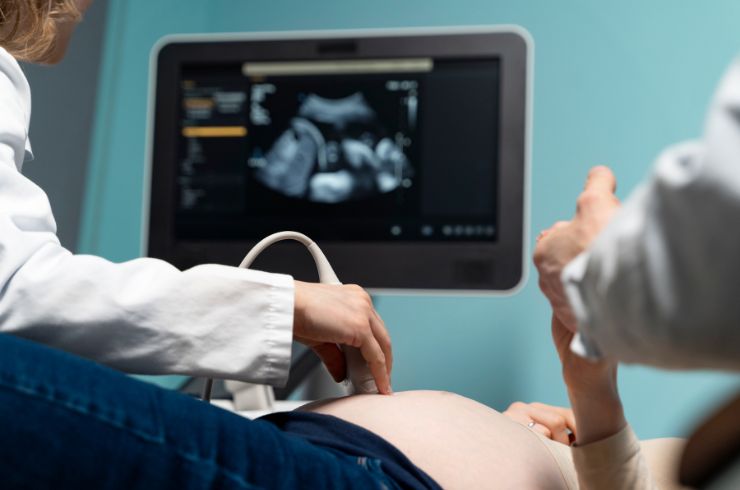

Equipped with advanced ultrasound machines, we ensure high-resolution imaging for precise, fast, and safe diagnostic evaluations by expert radiologists.

Adding further strength to the hospital’s reputation is Dr. Aarifa Aadil, a gold medalist gynecologist and radiologist trained at KGMU Lucknow. With over 14 years of experience, including work with Indira IVF Delhi, she provides high-quality ultrasound diagnostics using advanced 3D/4D imaging, as well as complete obstetric and gynecological care—from antenatal checkups